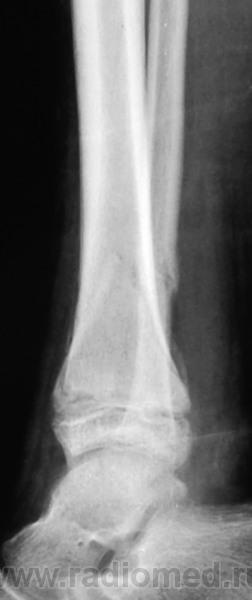

Сняли ГИПС...

Роно сняли или не срослось? А если не срослось, то почему? Суставную щель плохо видно.

Костная мозоль слабая.

Не срослось.

Не очень хорошее смещение в вальгус, что может привести к нежелательным последствиям. Обычно после репозиции таких переломов необходимо наложить гипс в положении варусной гиперкоррекции, в противном случае такие вторичные смещения - нередкость...

Если по-нормальному, то - остеоклазия с коррекцией оси, фиксация спицами (опционально, но желательно для предотвращения вторичного смещения) либо без фиксации (менее желательно). И конечно, гипс в положении коррекции.

Либо просто продление иммобилизации с осевой нагрузкой в гипсе (это если как обычно).